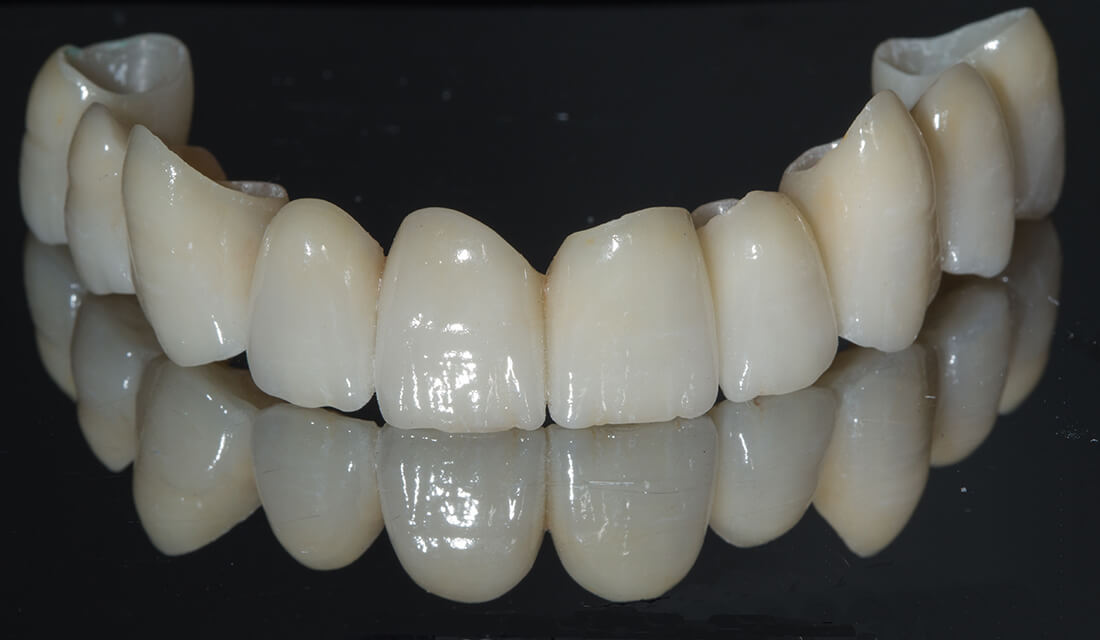

Corone Protesiche in Ceramica Integrale Stratificata

- Fisse, cioè saldamente connesse ai denti naturali (capsule metaliche e in ceramica, ponti) o, in assenza di elementi dentali a cui ancorarsi, fissate alle mascelle (riabilitazioni implanto-protesiche), possono essere confezionate con diversi materiali;